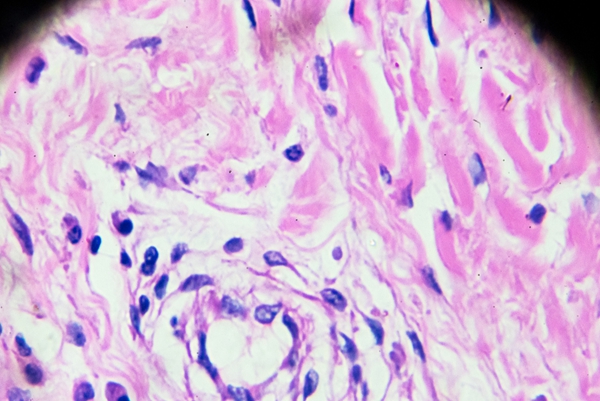

适用情况:当醋酸白试验或其他检查发现可疑病变时,可进行病理活检。通过手术切除或局部取材,对病变组织进行组织病理学检查。

诊断价值:病理活检是诊断HPV相关病变的“金标准”,可以明确病变的性质,如是否存在挖空细胞等特征性表现,有助于判断病情的严重程度。

过程:采集病变部位的细胞,制成涂片,在显微镜下观察细胞形态。可以发现一些异常细胞,对HPV感染的诊断有一定的辅助作用。